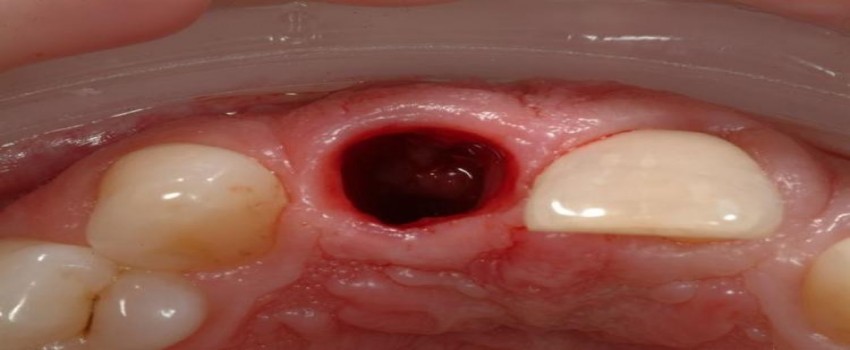

حفره خشک معمولا بعد از کشیدن دندان بوجود میآید. بعد از کشیدن دندان، لخته خونی جهت حفاظت از استخوانها، اعصاب و بافت ایجاد میشود. وقتی حفره خشک رخ دهد، در واقع خبری از لخته شدن خون نیست و ممکن است به اعصاب و استخوانها آسیب بزند.

بعد از کشیدن دندان ممکن است فرد دچار حفره خشک شود، اما دلیل مشخصی برای بروز این عارضه وجود ندارد. چند عامل باعث تشدید حفره خشک میشود که در اینجا به مهمترین این عوامل اشاره کردهایم:

دندانپزشک برای درمان حفره خشک، راههایی ارائه میدهد تا از درد بیمار کاسته شود. از جمله کارهایی که دندانپزشک در این خصوص انجام میدهد، عبارت اند از:

بعد از انجام این دسته از کارها توسط پزشک، بیمار باید تا چند روز در خانه نیز کارهایی برای التیام محل زخم انجام دهد: